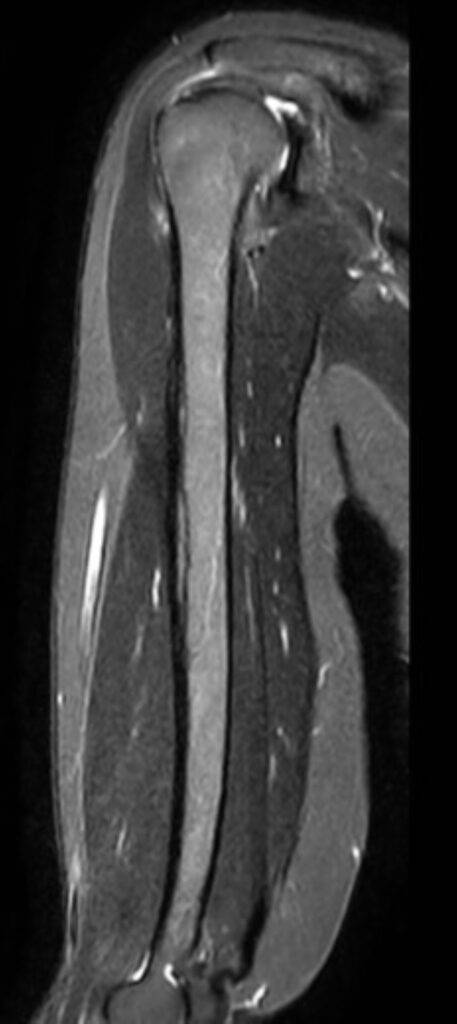

Die Magnetresonanztomographie der Schulter, kurz MRT Schulter genannt, ist eine bildgebende Untersuchung, die detaillierte MRT Bilder der Schulterstrukturen liefert, ohne Röntgenstrahlen zu verwenden. Sie ermöglicht die präzise Diagnose von Schulterschmerzen, Verletzungen, Arthrose und weiteren Erkrankungen der Schulter.

Eine Magnetresonanztomographie (MRT) oder auch Kernspintomographie der Schulter ist eine schmerzlose bildgebende Untersuchung, die ermöglicht die Strukturen im Schulterbereich präzise darzustellen. Es handelt sich hierbei um Querschnittbilder, die mithilfe von Magnetfeldern und Radiowellen ohne den Einsatz von ionisierender Strahlung erstellt werden. Mit der MRT können Knochen, Weichteile wie Muskeln und Sehnen, Gelenke sowie Nerven und Blutgefäße in der Schulterregion abgebildet werden. Dies ermöglicht die Diagnose von Schulterschmerzen, Verletzungen, Arthrose, Entzündungen und anderen Erkrankungen.

Was sieht man bei einer MRT Schulter?

| Gelenke und Knochen | Frakturen, Arthritis, weitere Gelenk-/Knochenprobleme |

| Bänder und Sehnen | Verletzungen oder Entzündungen |

| Schleimbeutel | Entzündung oder Schwellung |

| Rotatorenmanschette | Verletzungen oder Risse |

| Labrum | Verletzungen oder Risse |

| Nerven und Blutgefäße | Nervenkompression oder Gefäßveränderungen |